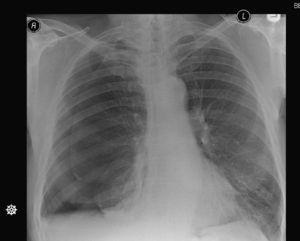

Patient 1A 71 year old male presented to the emergency department with a history of chest pain and shortness of breath. A chest X-ray (Fig. 1) showed a recurrent right hydropneumothorax, this was because in the previous two months, the patient had had two previous episodes of right pneumothorax which had been managed successfully by a right tube thoracostomy. He had no significant medical history. He was an ex-smoker with a 40 pack-year history. He also reported a heavy asbestos exposure in the past.

With the third episode, he was referred for surgical intervention while he still had the right-side tube thoracostomy in place. No chest CT-scan was performed.